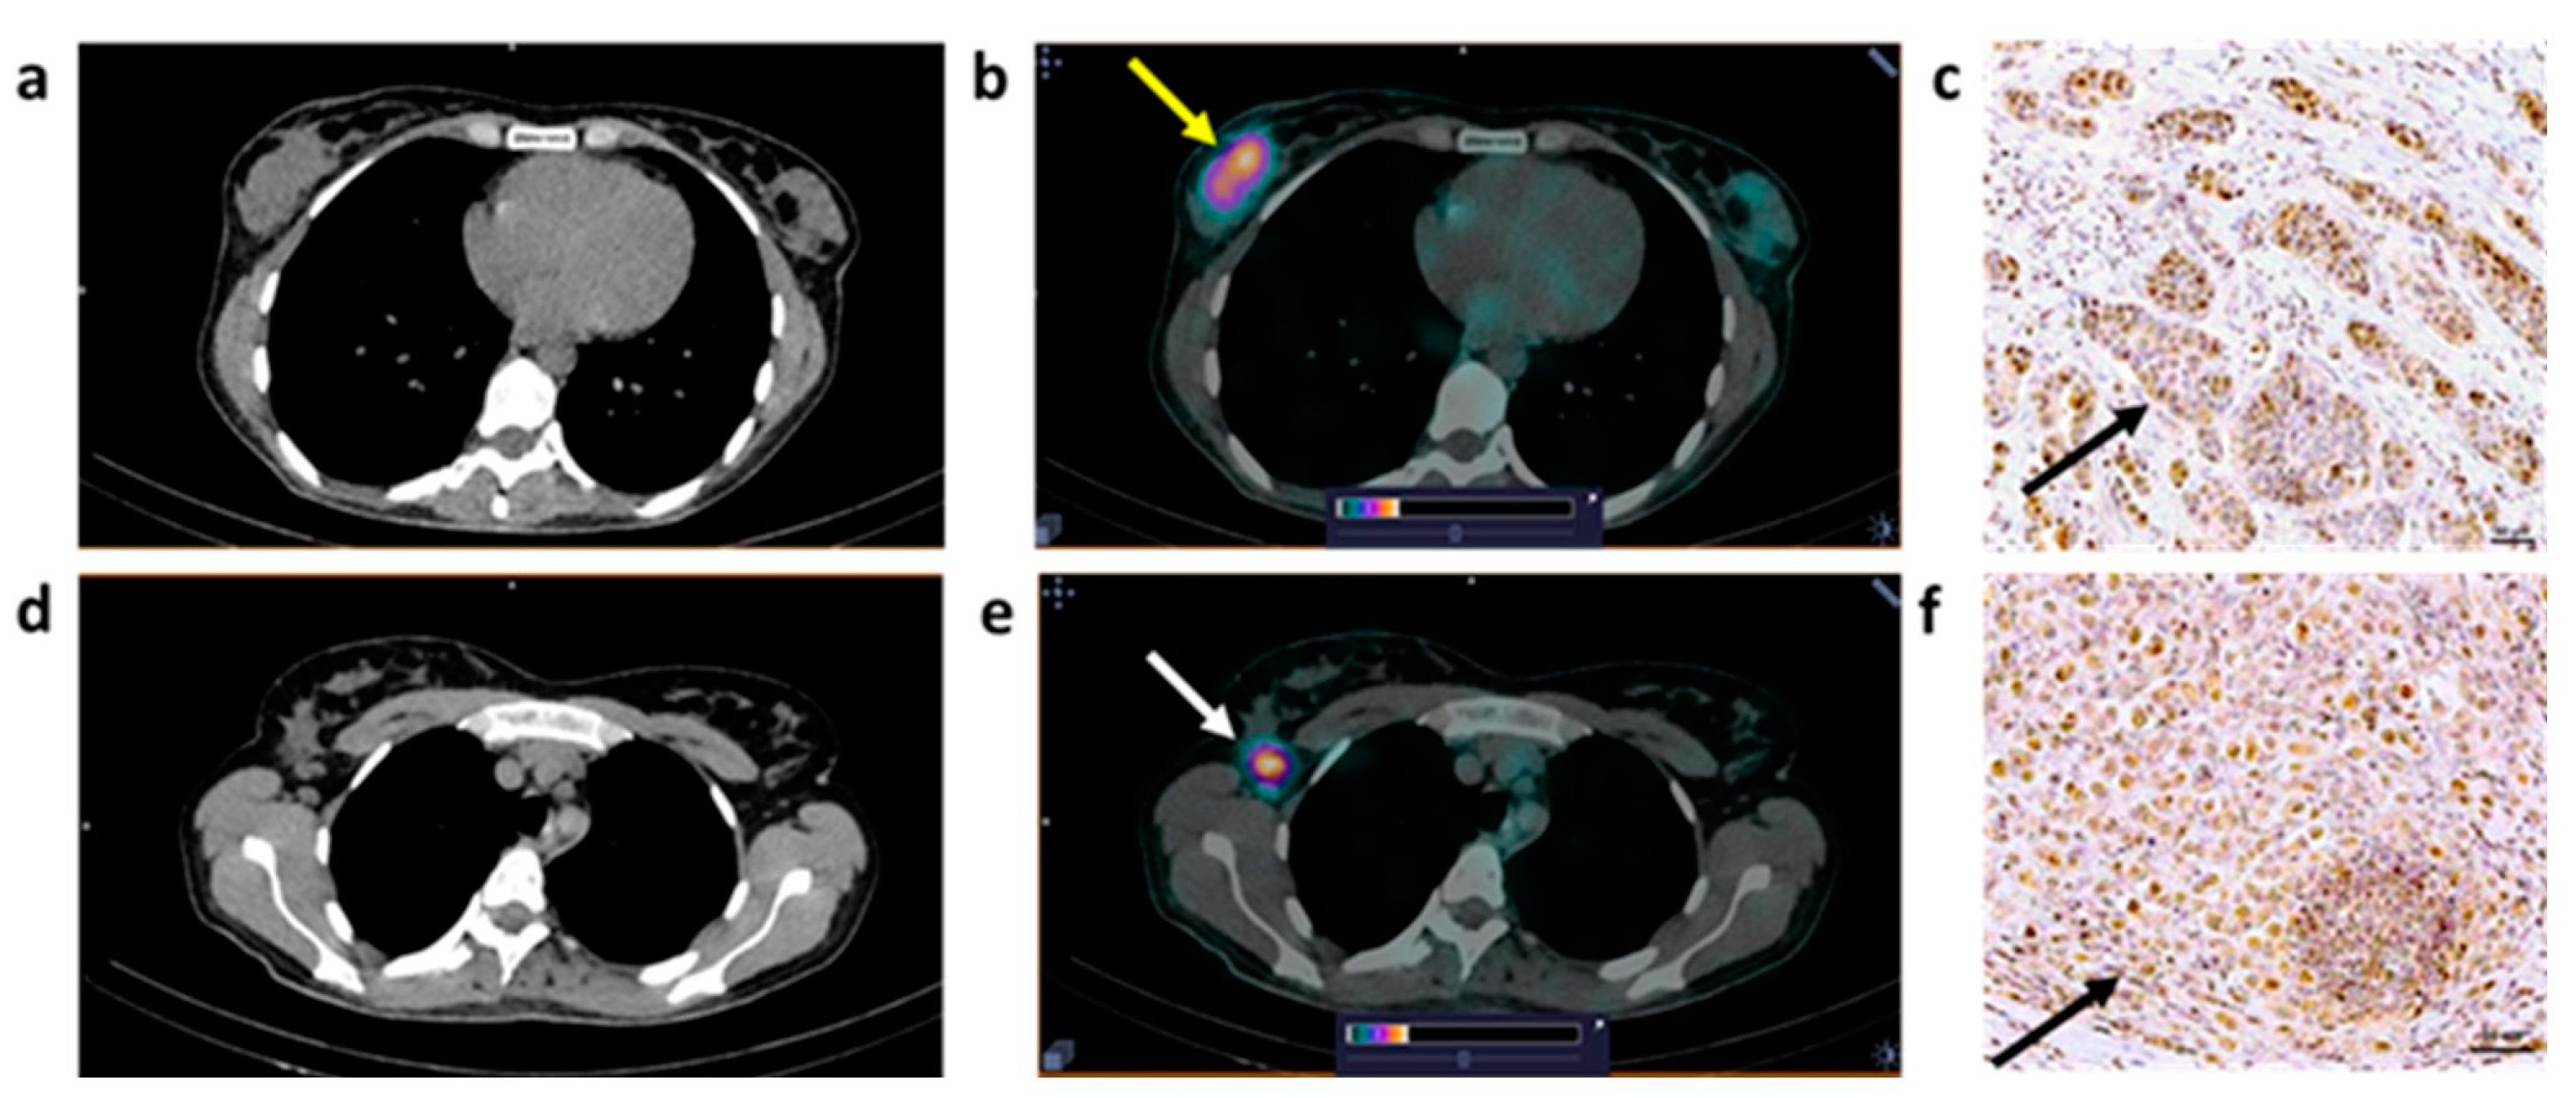

| B1 | 34 | IC NST G2 | T2N0M0 | T: 1.41 (2.8 × 2.2) | 2.2 | T: 3+ | T2N0M0 |

| B2 | 41 | IC NST G2 | T2N2M0 | T: 1.75 (3.8 × 2.2) LNM: 1.8 (1.3) | T: 35 LNM: 16.3 | T: 1+ LNM: 2+ | T2N3M0 |

| B3 | 40 | IC NST G2 | T2N0M0 | T: 0.87 (5.1 × 2.2) LNM: 1.8 (1.4) | T: 10.8 LNM: 7.1 | T: 0 LNM:1+ | T3N3M0 |

| B4 | 69 | ILC G1 | T2N0M0 | T: 0.57 (6.8 × 3.2) LNM: 0.58 (2.5) | T: 7.8 LNM: 6 | T: 1+ LNM: 1+ | T2N1M0 |

| B5 | 56 | IC NST G2 | T2N1M0 | T: 0.87 (4.0 × 1.7) LNM: 1.8 (2.3) | T: 14.5 LNM: 11.3 | T: 0 LNM: 0 | T2N1M0 |

| B6 | 50 | IC NST G1 | T1N0M0 | T: 0.43 (1.5 × 1.5) | T: 4.3 | T: 3+ | T1N0M0 |

| B7 | 62 | IC NST G2 | T1N0M0 | T: 0.50 (1.5 × 1.4) | T: 2.7 | T: 1+ | T1N0M0 |